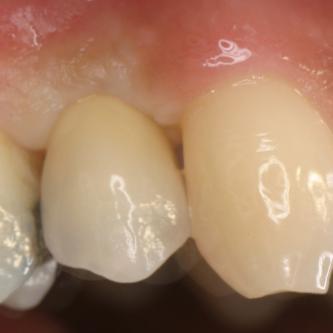

Exemple 2: Un implant remplaçant la racine d'une molaire inférieure gauche.

Exemple 2: La couronne en céramique scellée sur cet implant.